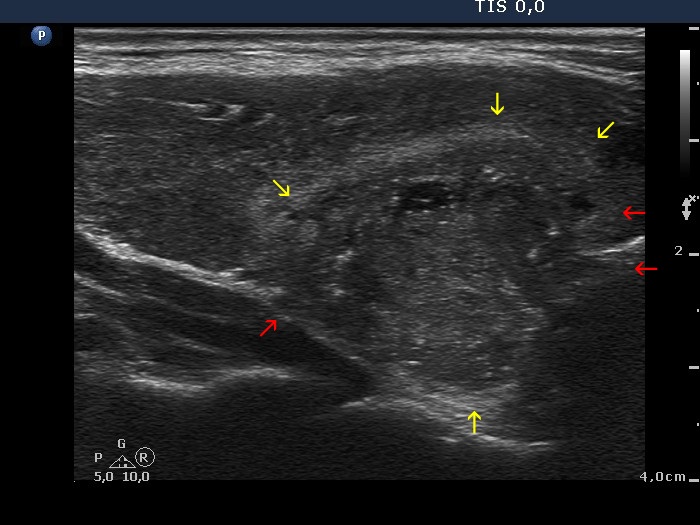

Papillary carcinoma (histology) - case conp005

Transverse scan

Longitudinal scan

The main body of the tumor is pointed with red arrows, while yellow arrows point to infiltration of the parenchyma. The hallmark of these areas is the presence of microcalcifications.